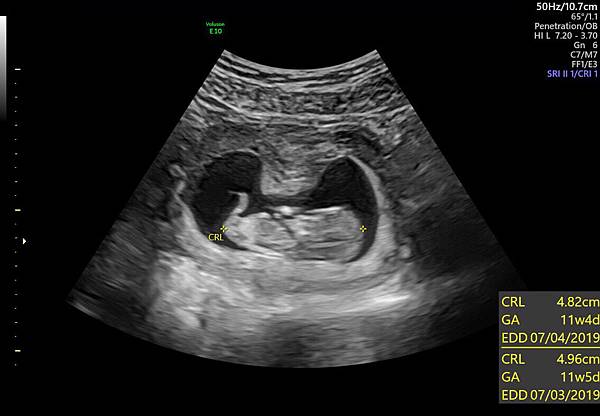

附上檢查後的幾張影像,和一張外星人的3D照。

下面為寶寶今天趴著的特寫,有乖乖長大喔。